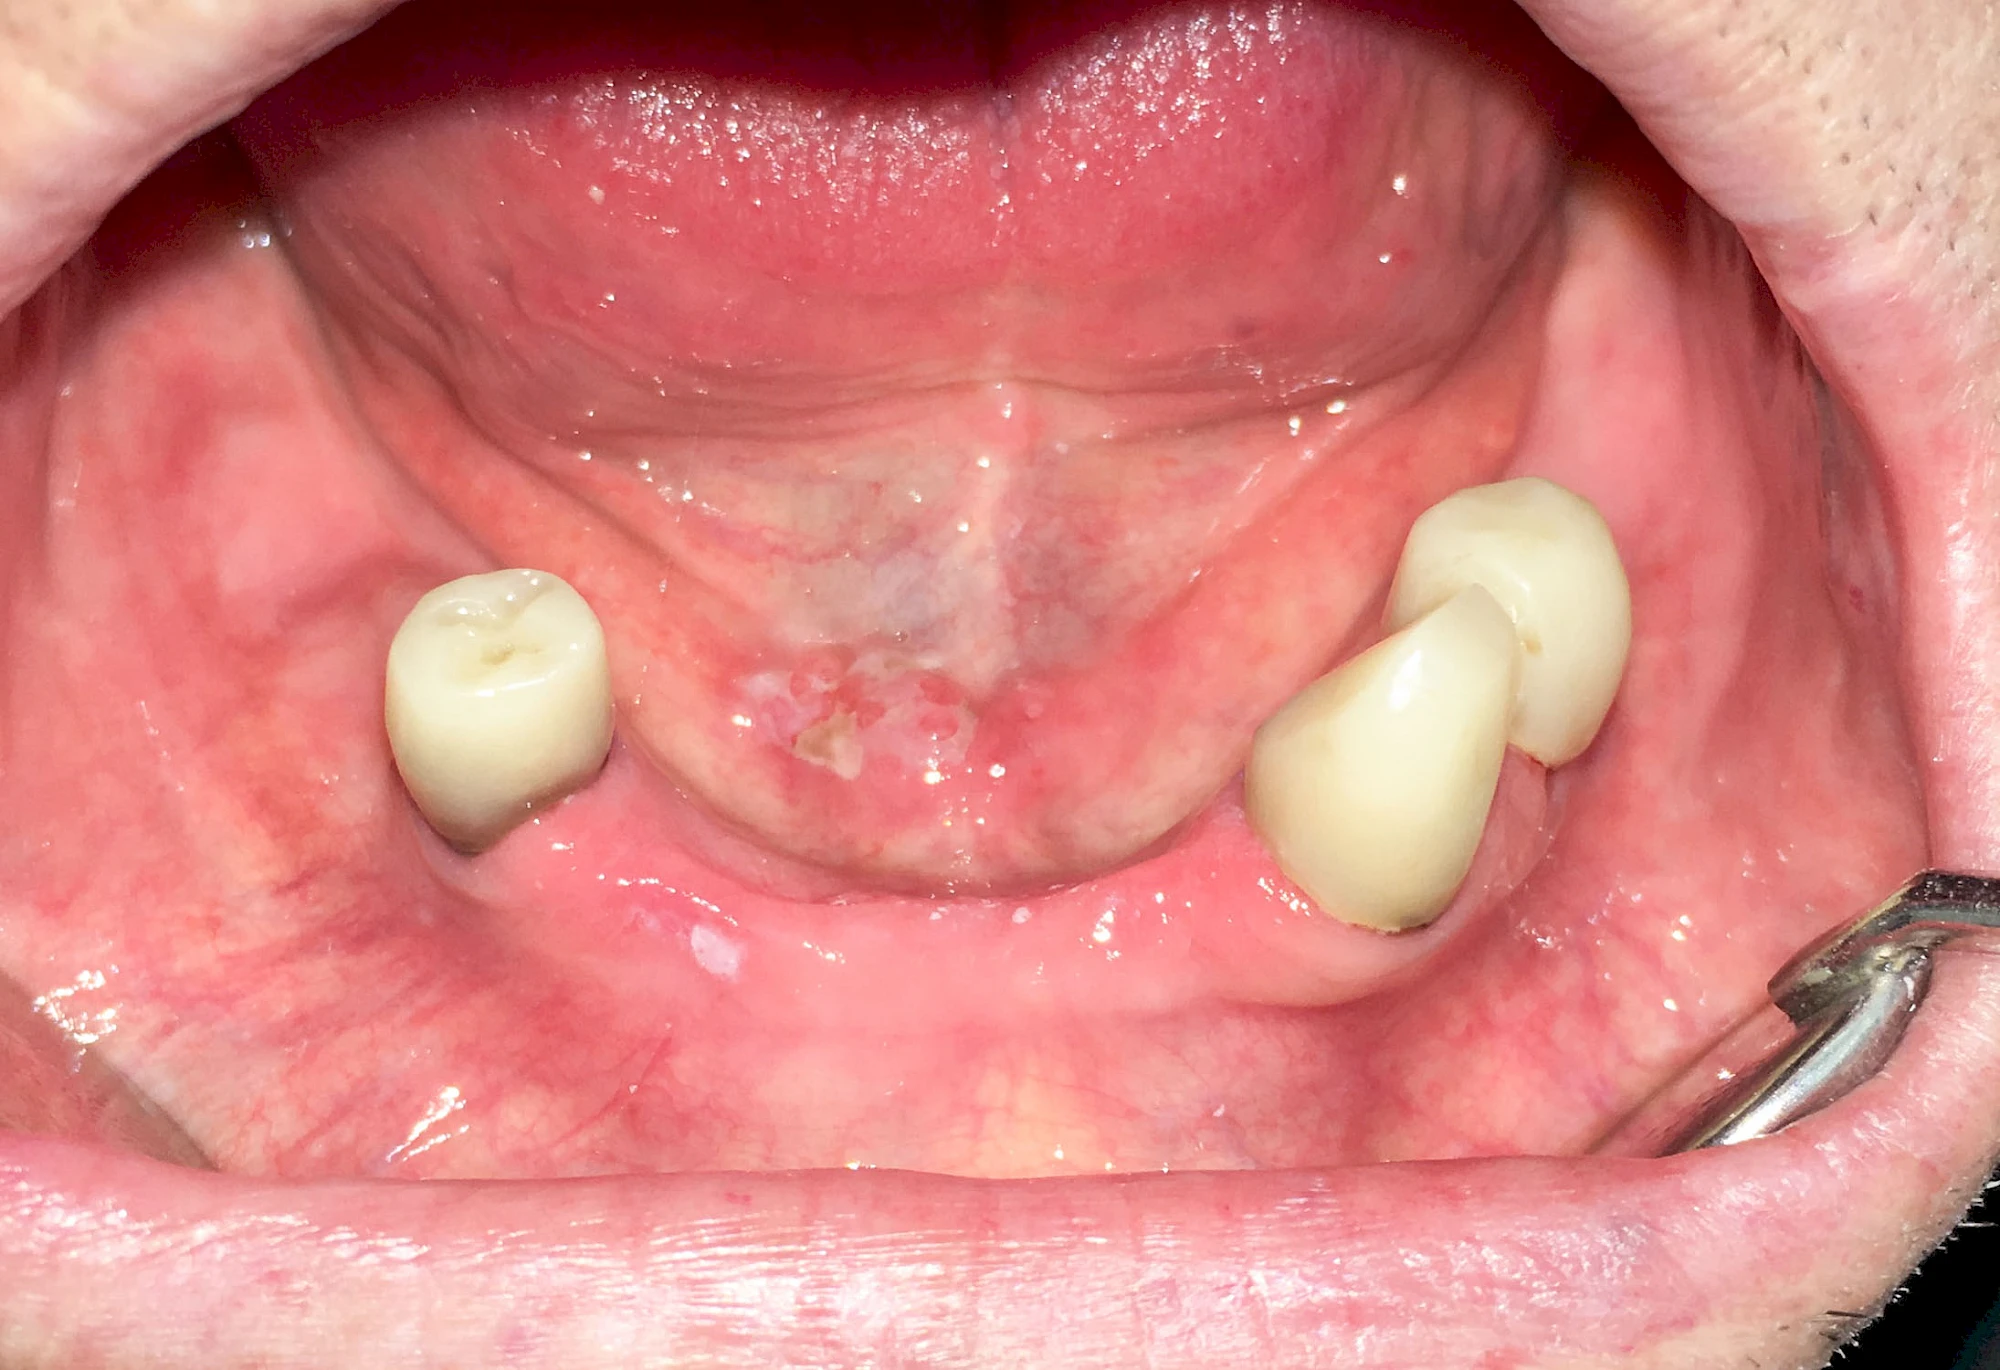

Speicheldrüsenzyste

Eine Speicheldrüsenzyste (Speicheldrüsenretentionszsyte) kann als Schwellung oder Auftreibung meist im Bereich der größeren Ausführungsgängen auffallen, wenn z. B. ein Speichelstein den Speichelfluss behindert. Vor allem bei den Mahlzeiten, wenn der Speichelfluss angeregt wird, nimmt die Auftreibung oder Schwellung schmerzhaft weiter zu. In der Regel ist die Unterkieferspeicheldrüse (Glandula sublinugalis) betroffen. Man spricht dann auch von einer Frosch- bzw. Fröschleingeschwulst (Ranula). Bringt sanftes Massieren der Schwellung bzw. Auftreibung keine Verbesserung, sollte ein Arzt oder Zahnarzt hinzugezogen werden